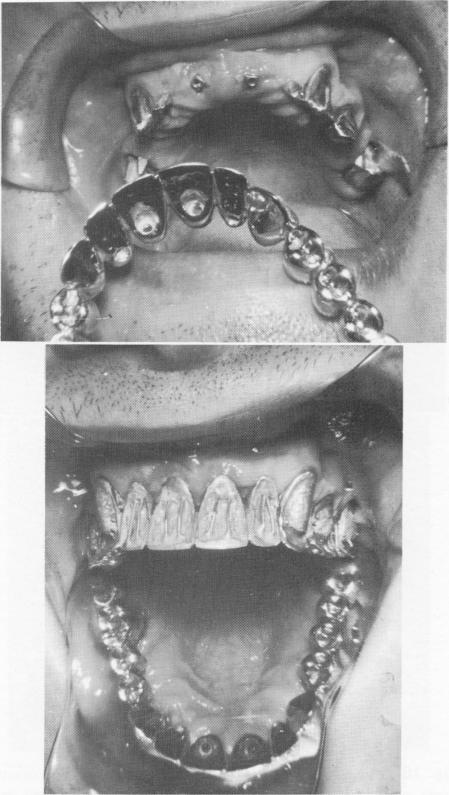

At the next visit, the copings comprising the mesostructure were fitted over the prepared abutment teeth (Fig. 10-193). Two internally threaded vent-plants were then screwed into the right and left maxillary central incisor regions until only about 1 mm. of their shafts protruded out of the fibromucosal tissue (Fig. 10-194). The veneer crown superstructures were then placed over the mesostructures (Fig. 10-195) and a wax interocclusal record of centric relation and a full mouth plaster index were taken( Fig. 10-196).

The full arch gold framework was tried in the mouth, and all necessary adjustments were accomplished (Fig. 10-198).

Fig. 10-198. The soldered full arch denture is tried in position.